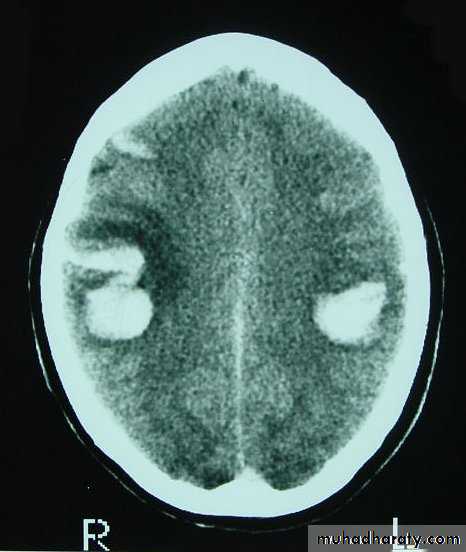

b. Subdural Haematoma

They are the most common intracranial mass lesions resulting from head trauma.

They are classified depending on how long they take to present clinically following the injury into:

Acute Subdural Haematoma: less than 3 days

Subacute Subdural Haematoma: 4-21 days

Chronic Subdural Haematoma more than 21 days.

Acute Subdural Haematoma

Usually due to MORE SEVER high velocity trauma and thus associated with a poorer outcome.

Source of bleeding (haematoma): include:

Most result from torn bridging veins or focal tears of a cortical artery.

Cortical lacerations or contusions.

Bleeding from tears in the dural venous sinuses.

Clinical Picture: patient will present with a picture similar to that of an extradural haematoma, but there is persistent loss of consciousness with no lucid interval.

Ct scan will show a concave hyperdence collection because blood follows the subdural space over the convexity of the brain.

Acute Subdural Haematoma are rapidly evolving lesions and early evacuation via craniotomy is mandatory.